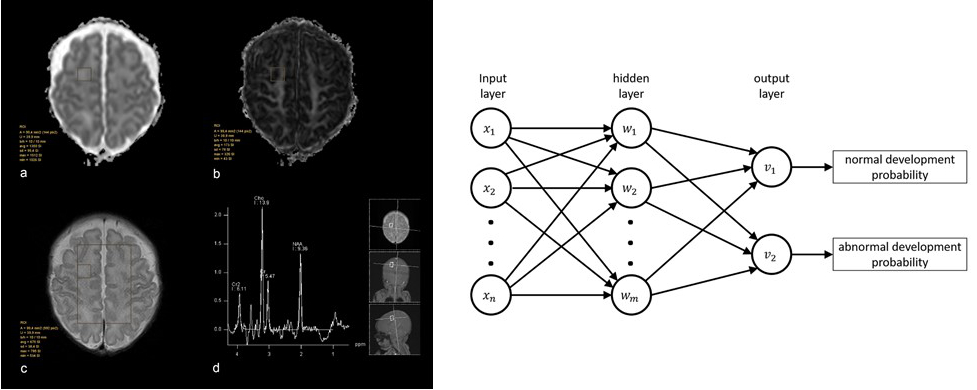

MRI and MRS Parameters in the Cerebral Development of Preterm Infants

Dr. Djurdjevic, Prof. Gizewski and Dr. Pereverzyev in cooperation with Prof. Kiechl-Kohlendorfer and Prof. Buchheim (LFU)

In this prospective study into multimodal MRI in very preterm neonates (< 32 gestational weeks), we employed feed-forward neural networks (fNNs), a segment of artificial intelligence. We showed that fNNs might be a useful predictive tool for cognitive and motor outcome prediction in very preterm neonates when using cerebral 1H-MRS and DTI biomarkers (Fig. 3). Moreover, by combining these sophisticated methods, the predictive value of MRI can be significantly increased. Further applications are now being tested in a larger cohort.

Fig. 3: An example of region-of-interest-based evaluation of ADC (a) and FA (b) in frontal white matter on the right side with a corresponding voxel in 2D CSI 1H-MR spectroscopy (c, d).

A network diagram on the right, representing the neural networks employed in the MRS and DWI data of preterm children.

Each unit of the input and hidden layer connects to each unit of the subsequent layer. Through these connections, every unit of the hidden and output layer is a linear combination of all units of the preceding layer followed by a non-linear transfer function. The input units xj correspond to the variables used for class prediction (metabolite ratios and DTI characteristics).